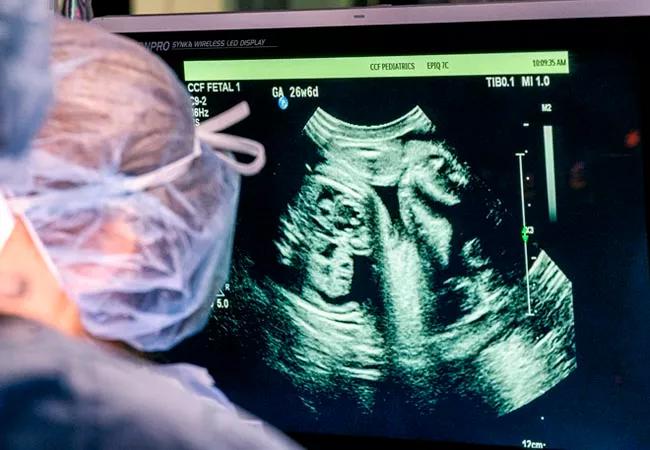

When a potential fetal cardiac defect is identified during a screening ultrasound, referral to Cleveland Clinic Children’s Fetal Cardiac Care Center should be the next step.

“We confirm the diagnosis with an echocardiogram focused on the heart and discuss the findings with the parents. Then we introduce them to the other services they will need,” says Dr. Erenberg.